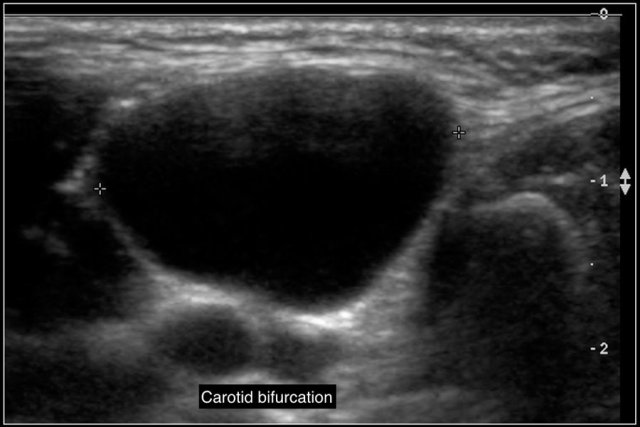

They are located along the anterior border of the sternocleidomastoid muscle, lateral to the common carotid artery, and if more cranially between the internal and external carotid artery.

Sometimes a beak sign may be seen as a curved rim of the lesion pointing medially between the internal and external carotid.

On ultrasound they often contains internal echoes caused by debris, which consists of cholesterol crystals.

The cyst is usually compressible, which results in movement of the content.

Here another branchial cyst with a typical location superficial to the carotid artery bifurcation.